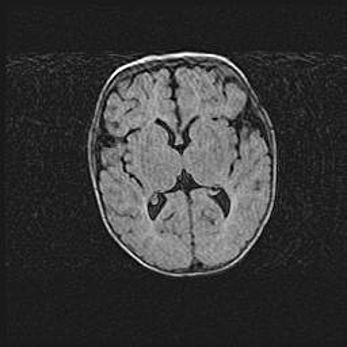

Наружная гидроцефалия с возможной атрофией височных областей.

Возраст: 28 дней

Вес: 3670 г

Пол: мужской

Окружность головы: 38 см

Срок гестации: 40 недель

Гидроцефалия головного мозга у новорожденных – это заболевание, которое характеризуется скоплением избыточного количества спинномозговой жидкости в желудочковой системе головного мозга в результате затруднения её перемещения от места выработки к месту поглощения в кровеносную систему или вследствие нарушения абсорбции. При открытой наружной форме гидроцефалии у новорожденных расширяются и переполняются субарахноидные пространства.

При нормотензивных  формах,  которые,  как  правило,  являются  следствием  перенесенных ишемических  повреждений  паренхимы  мозга,  возможно  сочетание микроцефалии  с нормотензивной гидроцефалией. В основе данных изменений лежит атрофия больших полушарий с преимущественной  локализацией  в  лобно-височных  областях.